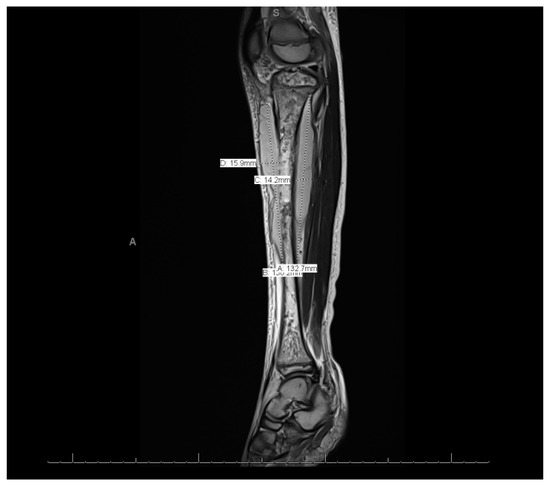

MRI of the left leg (Figure 3 and Figure 4): The whole left tibial bone shaft (proximal, mid, and distal), including the proximal epiphysis, showed a diffuse, multiple, heterogeneous marrow signal, intermediate to low on T1 and high on T2, as well as bone marrow edema associated with a periosteal reaction seen mainly on the medial aspect of the proximal metaphysis of the tibia. This is a large lobulated/septated periosteal collection surrounding all aspects of the proximal region and the mid-shaft of the left tibia bone. The collection ran along posteriorly for a distance of 13.3 cm × 3.2 cm × 1.4 cm (cranio-caudal [CC], medial–lateral [ML], and anterior–posterior [AP], respectively), with a small pocket extending to the posterior muscle compartment involving the knee joint, which showed joint effusion and synovitis. The anterior part of the collection extended partially to the anterior subcutaneous area and measured 13 × 5.7 × 1.6 (CC, ML, and AP, respectively). Both the anterior and posterior parts of the collections were connected. A focal cortical defect was evident at the anterior medial aspect of the proximal tibial epiphysis (T2 STIR axial 15/44 image), with an adjacent periosteal collection. The fibula, femur, and ankle joint were not involved and showed a normal signal. Diffuse soft tissue swelling was evident, mainly in the proximal part of the leg. The muscles around the leg and knee joint appeared to be normal. The MRI findings were in line with acute osteomyelitis of the left tibia, with periosteal collections.

Figure 3.

Magnetic resonance imaging of the whole left leg.

This case showed distant metastatic emboli to the left leg. Other studies showed different sites, such as the lungs [10]. Similarly to other cases, this case was treated without surgical interventions because there was no obvious surgical necrosis that necessitated debridement, and cases requiring surgical interventions are rare [10]. The sign that indicated migration was that swelling of the left leg began after the fever onsite. In addition, the imaging modalities for this patient, including MRI, indicated migration.